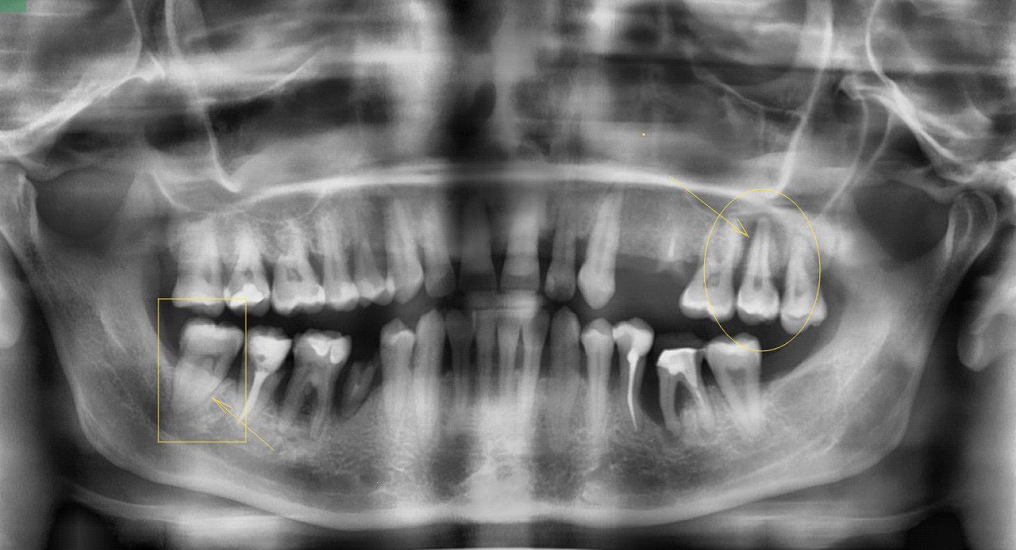

Вот, собственно, оценка состояния прилегающих тканей:

В прямоугольнике относительно сохранная периодонтальная щель, в овале — расширенная. Это признак воспаления.